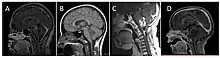

| Brain stem glioma. MRI axial, with contrast | |

A brainstem glioma is a cancerous glioma tumor in the brainstem. Around 75% are diagnosed in children and young adults under the age of twenty, but have been known to affect older adults as well.[1] Brainstem gliomas start in the brain or spinal cord tissue and typically spread throughout the nervous system.[2]

Neuroimaging, such as MRI, is the main diagnostic tool for brain stem gliomas. In very rare cases, surgery and biopsy are performed.